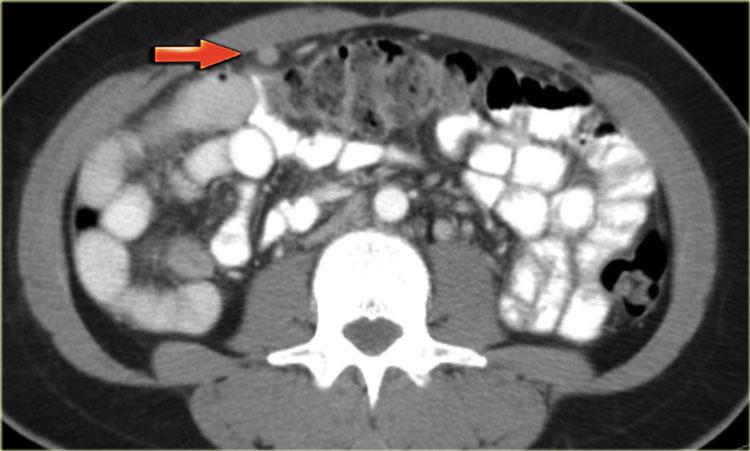

Hình CT cho thấy các khối nang phức tạp ở cả hai buồng trứng.

Mặc dù ung thư biểu mô tuyến nang thanh dịch có thể xuất hiện hai bên, nhưng loại này thường có dạng đơn thùy hơn là đa thùy.

Hầu như không nhìn thấy một phần của ung thư đại trực tràng dạng vòng nhẫn (mũi tên xanh).

Nhìn thấy rõ ràng là các tổn thương cấy ghép dạng nang trên phúc mạc phản chiếu (mũi tên đỏ).

Đây là các tổn thương di căn buồng trứng dạng nang của ung thư đại trực tràng.